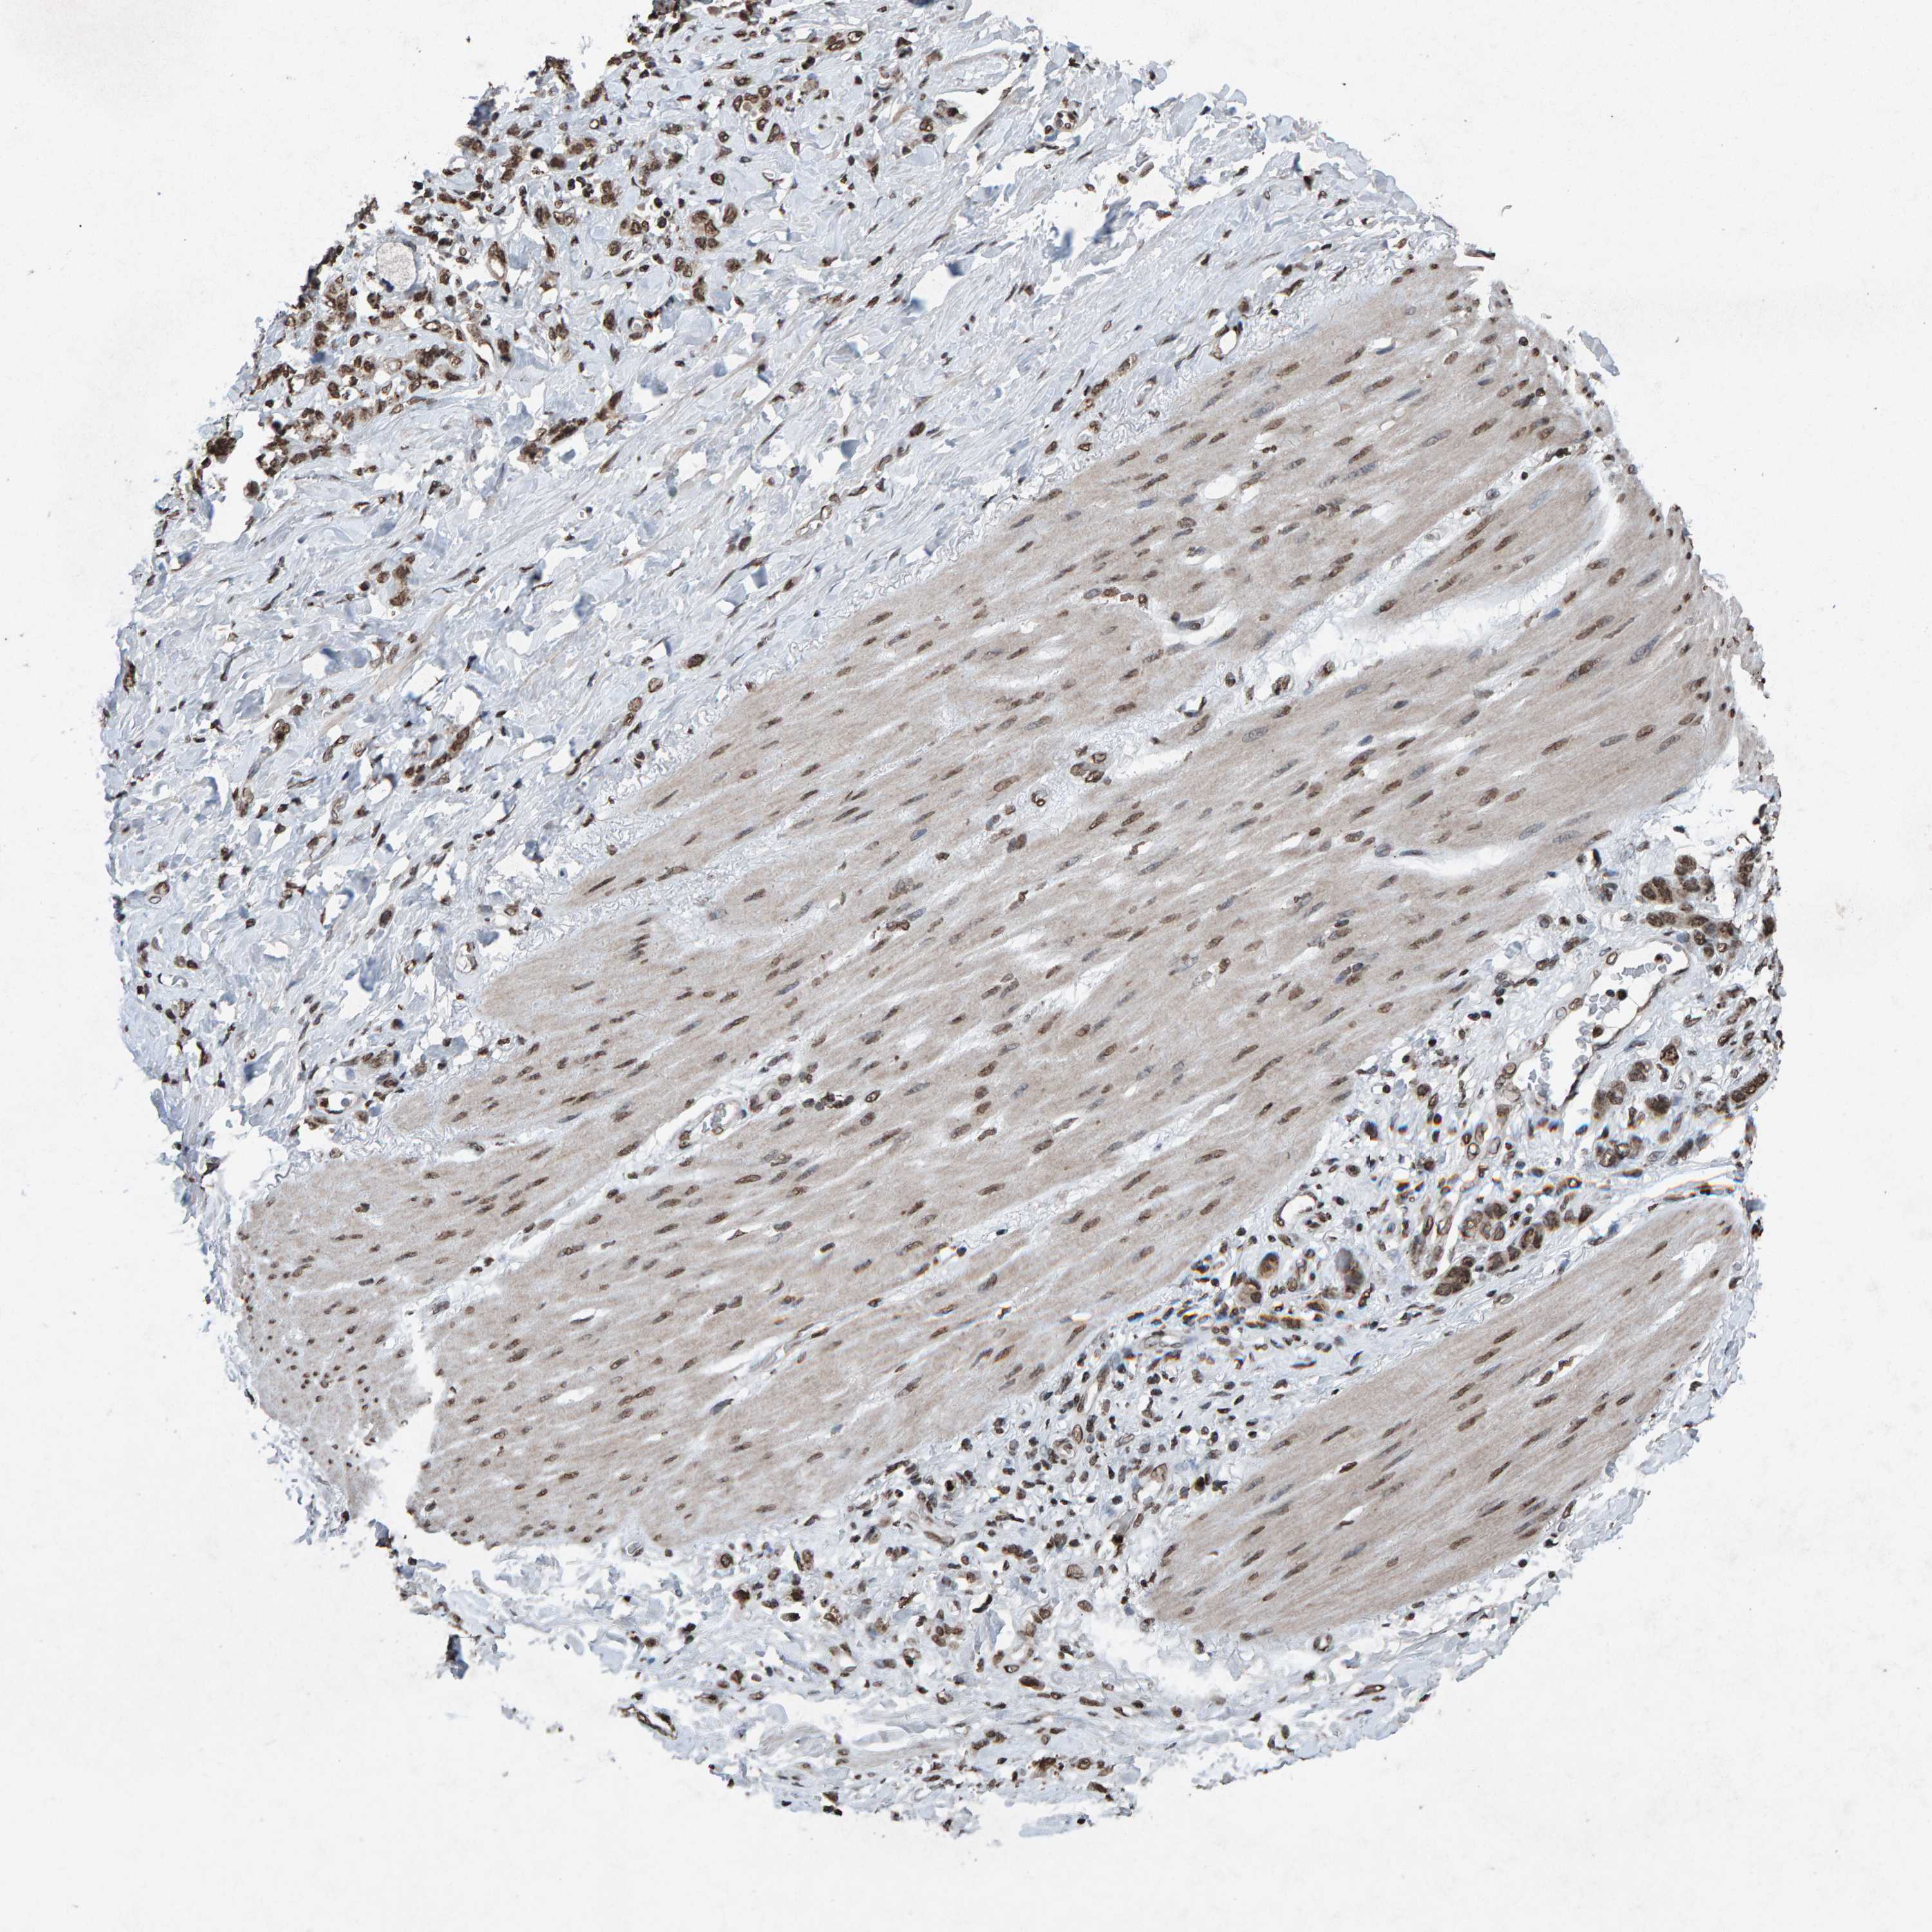

STOMACH CANCER - Protein expressioni

A mouse-over function shows sample information and annotation data. Click on an image to view it in a full screen mode. Samples can be filtered based on level of antibody staining by selecting one or several of the following categories: high, medium, low and not detected. The assay and annotation is described here.

Note that samples used for immunohistochemistry by the Human Protein Atlas do not correspond to samples in the TCGA dataset.

Antibody stainingi

Antibody staining in the annotated cell types in the current human tissue is reported as not detected, low, medium, or high, based on conventional immunohistochemistry profiling in selected tissues. This score is based on the combination of the staining intensity and fraction of stained cells.

Each image is clickable and will lead to virtual microscopy that enables deeper exploration of all samples and also displays staining intensity scores, fraction scores and subcellular localization as well as patient and tissue information for each sample.

Antibody HPA057236

Antibody CAB022549

Staining

High

Medium

Low

Not detected

Intensity

Strong

Moderate

Weak

Negative

Quantity

>75%

75%-25%

<25%

None

Location

Nuclear

Cytoplasmic/membranous

Cytoplasmic/membranous,nuclear

Adenocarcinoma, NOS

Adenocarcinoma, High grade